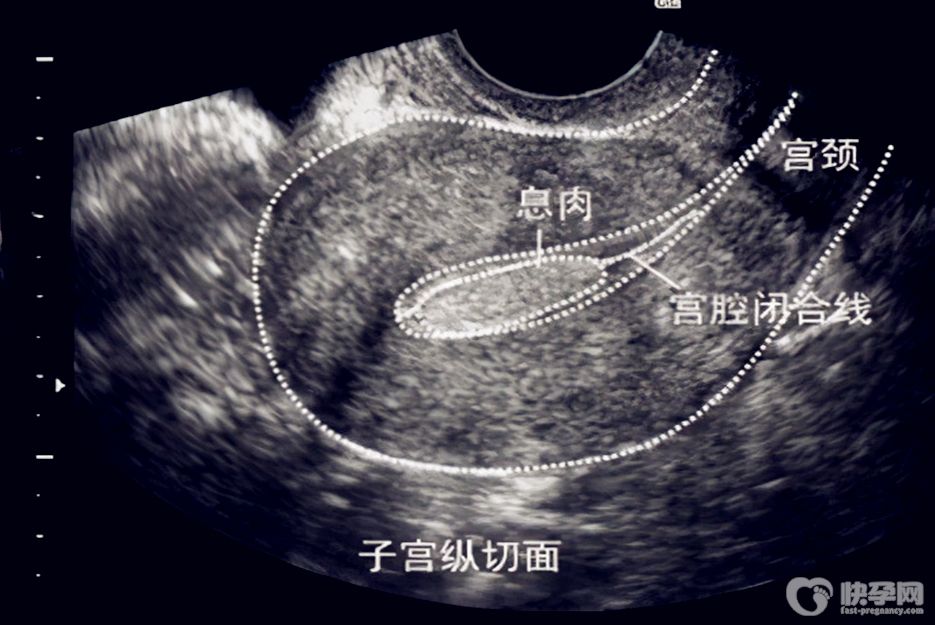

子宫内膜息肉是一种常见的妇科疾病,绝大多数都是良性的。子宫内膜是子宫内壁的一层,正常情况下应该是比较平整的,当子宫内内膜局部过度生长就会导致子宫内膜息肉,可表现为突出子宫腔的单个或多个肿物。大多数患者没有症状,有的表现为子宫异常出血。

B超检查可以很容易发现息肉,另外在做超声造影的时候,通过三维超声成像也可以很容易发现子宫内膜息肉,当然子宫内膜息肉诊断的“金标准”是宫腔镜,可以明确是否存在息肉、息肉的大小、位置以及形状。